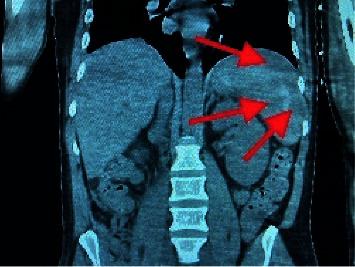

Here, we present a unique case of a 38-year-old male with a history of alcohol use disorder and multiple sexual partners, who presented with fulminant sepsis with shock, multiorgan failure, and livedo racemosa after a dog bite the week prior. The patient was intubated on arrival and was started on vasopressors and antibiotics. Eventually, the patient's clinical status improved, and he was transferred out of the intensive care unit. Blood cultures tested positive for oxidase-positive Gram-negative rods two days after collection, and species identification showed .

在此,我们报告一例独特病例,一名38岁男性,有酒精使用障碍病史且有多个性伴侣,在一周前被狗咬伤后出现暴发性脓毒症伴休克、多器官功能衰竭和网状青斑。患者入院时即行气管插管,并开始使用血管升压药和抗生素。最终,患者的临床状况有所改善,并转出重症监护病房。血培养在采集两天后检测出氧化酶阳性革兰氏阴性杆菌呈阳性,菌种鉴定显示……